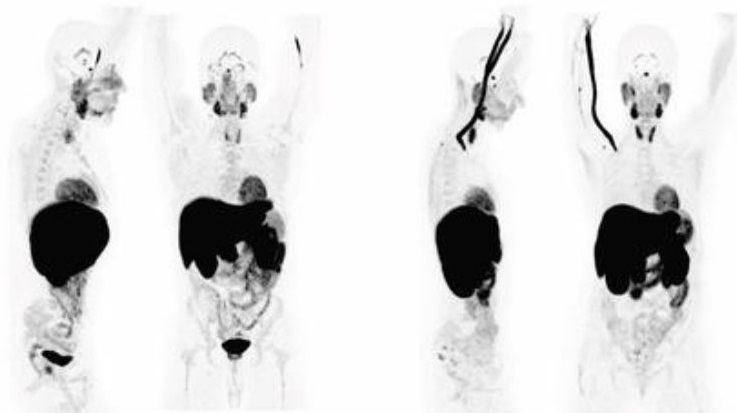

Foto: Shutterstock, M. M./ATAImages Foto: Shutterstock, M. M./ATAImages Foto: Shutterstock, M. M./ATAImages Snimljeni za vikend, na rezultate čekaće nedeljama: Šta ne štima u Lončarevoj tvrdnji da su ukinute liste čekanja za skener autor: Ana Marković Društvo 26. sep. 2024. 17:06 6 Podeli vest: Ministar zdravlja Zlatibor Lončar tvrdi da u Srbiji više nema listi čekanja za skener, jer je proteklog vikenda pregledano gotovo 3.000 ljudi. Međutim, prećutao je da time problem nije rešen, jer će dobar deo pacijenata čekati na rezultate nedeljama ili mesecima, jer u našoj zemlji postoji ozbiljan deficit radiologa, čiji je posao snimanje i pisanje ovih izveštaja, a njihov nedostatak uzrokovaće i nove liste. Podeli vest: Oglas Prema statistikama zdravstvenih kadrova, radiolozi su u srpskoj medicini među najdeficitarnijim, pa su traženi i državno i privatno, zbog čega svi rade duplo, a u ustanovama se tako formiraju liste čekanja na snimanja, ali i na rezultate. Uzrok višemesečnog čekanja bio je, ističu stručnjaci, upravo deficit radiologa, koji izdaju rezultate pregleda, koje pacijenti u državnim bolnicama često ne dobiju i po nekoliko nedelja, zbog gužve. Poliklinika Urgentnog kliničkog centra Foto:TANJUG/ TANJUG VIDEO | Poliklinika Urgentnog kliničkog centra Foto:TANJUG/ TANJUG VIDEO “Do 2012. radio sam u Univerzitetskom kliničkom centru Niš. Tamo se mesecima čekalo na snimanja, za skener čak kraće nego za magnet. Jedno vreme radili smo i treću smenu, pa su nam to ukinuli. Zbog deficita osoblja, diskutabilan je broj snimljenih tokom proteklog vikenda, koji pominje ministar Zlatibor Lončar. Nije mi jasno gde su pronašli toliko tehničara i radiologa, ali i ispravnih skenera. Trebalo bi da negde bude transparentno izdat taj spisak”, kaže za Nova.rs dr Aleksandar Ivković, specijalista radiologije. Radiolozi rade i državno privatno U privatnim ustanovama, rezultat se dobija odmah posle snimanja. “To je kad imate jednog, dva pacijenta, a ne desetine ili stotine njih. Međutim, čujem da u bolnicama ljudi i dalje čekaju rezultate 10 do 15 dana, pa i duže. Sve zavisi od broja pacijenata, ali i kadrova. Radiolozi rade privatno, bez obzira da li su zaposleni u državnoj ustanovi, jer je deficit veliki, a taj dupli posao usporava rad na rezultatima”, objašnjava dr Ivković. Foto:TANJUG/ NEBOJŠA RAUS | Foto:TANJUG/ NEBOJŠA RAUS Radiolozi, inače, ne bi smeli da rade prekovremeno. “Osim što je malo radiologa, oni po zakonu ne smeju da rade, odnosno da provode u zoni zračenja, duže od 32 sata nedeljno. A kako su zaposleni i državno i privatno, ne mogu da postignu da urade sva snimanja na vreme, ni da izdaju rezultate, posebno kad je veliki broj pacijenata u kratkom periodu, kao što je bio slučaj proteklog vikenda”, ističe doktor. Kako radi skener? Posle više godina prakse u državnoj bolnici u Beogradu, viši radiološki tehničar, koji je zamolio da ostane anoniman, za Nova.rs objašnjava koliko je zapravo složena procedura snimanja skenerom i pisanje izveštaja, ali i zbog čega kolege iz struke sumnjaju u broj izvedenih snimanja, koje ministar navodi. “To nije nešto što se radi ‘preko noći’, niti za pet minuta. U pitanju je ozbiljna dijagnostika koja nekome može spasiti život ako se uradi kako treba, a može napraviti problem, ako se ne radi pažljivo i pravilno. Nadam se da te ljude nisu ofrlje pregledali, jer veliki je to broj za samo dva dana. Skenerski pregled, na današnjim MDKT aparatima traje od par minuta (ako je hitan pregled traume glave), pa do oko 15 minuta, na primer pregledi urološke patologije”, priča on. Besplatni pregledi pacijenti Foto:TANJUG/ RADE PRELIĆ | Besplatni pregledi pacijenti Foto:TANJUG/ RADE PRELIĆ Skenerskom pregledu prethodi, ističe, uobičajeno "dobar dan, ime i prezime, laboratorijske analize”, kao i popunjavanje upitnika i slično, što oduzima određeno vreme. "Osoblje potom mora svakom pacijentu da objasni šta da radi, da se prvo raskomoti, šta sve da skine sa sebe, gde da legne. Onda se objašnjava da će mu u venu ruke postaviti plastičnu cevčicu, braunilu za davanje kontrasta (kod nekih), a da u narednih pola sata mora da popije rastvor, koji je gorak, ali sitnim gutljajima na po par minuta, pa bude lakše", nastavlja naš sagovornik. Foto:TANJUG/ NEBOJŠA RAUS | Foto:TANJUG/ NEBOJŠA RAUS Potom taj isti pacijent odlazi opet u čekaonicu. “Tamo sedi dok ne popije rastvor i čeka da opet bude prozvan. E, tek kada pacijenta prozovemo, sledi dva do 20 minuta pregleda, odnosno snimanja skenerom, koje zavisi od dela tela koje se snima. Nakon toga uzimamo ruku pacijenta i izvlačimo cevčicu, kada se oblači i slobodan je da ide. I to je procedura samo za jednog, a zamislite sad gotovo 3.000 ljudi”, kaže ovaj viši radiološki tehničar. Posle snimanja, red je na pisanje izveštaja I to je samo deo posla. Tek nakon snimanja, radiolog mora da interpretira pregled, odnosno da napiše šta je video. Foto: UCSF | Foto: UCSF “Tada daje svoje mišljenje o dijagnozi zbog koje je pacijent poslat na CT. Taj deo posla zahteva daleko više vremena od samog snimanja. Svaki deo pregledanog dela tela mora rečima da opiše, kvalifikuje i kvantifikuje (dimenzije, položaj sa susednim strukturama, ponašanje nakon ubrizgavanja kontrasta, itd.)”. Zamislite, naglašava on, šta sve treba opisati jednom onkološkom pacijentu, kome su skenirani grudni koš, abdomen i karlica. Foto: Nevena Milovanović/Promo | Foto: Nevena Milovanović/Promo “Kreće se od pluća - svaki deo ponaosob, pa veliki krvni sudovi sredogruđa, pa samo sredogruđe. Potom sledi dijafragma, pa tek onda ono najosnovnije u trbuhu ili karlici. E, to pregledanje urađenog skenera je najvažnija stvar, a pored znanja i iskustva iziskuje vreme. Radiolog treba da održi oko i pažnju satima na više pacijenata, da se, ne daj bože, nešto ne previdi ili loše interpretira (opiše). Na stranu što mora da prekida taj posao, u slučaju konsultacija sa tehničarem, ako nešto nije jasno”, objašnjava naš sagovornik. Koliko je radiologa i tehničara, ali i skenera, bilo uključeno u snimanja proteklog vikenda, kad će svi ti rezultati biti gotovi i koliko će biti sigurni, ako su “na brzinu” ispisani. “Za vikend smo, navodno, ukupno snimili gotovo 3.000 pacijenata, a niko ne pominje nalaze. Ovo je sve, plašim se, jeftini populizam i ‘rešavanje’ problema preko kolena, koje ne može da se održi na duže staze i vrlo je upitno“, zaključuje viši radiološki tehničar. *** BONUS VIDEO: Nema više listi čekanja za skener Lončar: U Srbiji više nema liste čekanja za pregled skenerom Društvo 18 “Ministre, mi smo tu. Ne morate da čekate Vučića, on je samo pravnik”: Lekari o skandaloznoj izjavi Lončara Društvo 43 Lončar: Za rešavanje lista čekanja potreban dodatni novac, zato čekamo Vučića Društvo 10 Uzalud nam rendgeni kad nema radiologa: Objašnjenje predsedniku Vučiću Društvo 0 liste čekanja skener Zlatibor Lončar Pratite nas na društvenim mrežama: Koje je tvoje mišljenje o ovoj temi? Učestvuj u diskusiji ili pročitaj komentare Budite prvi koji će ostaviti komentar Pošalji komentar Pročitaj komentare (6)